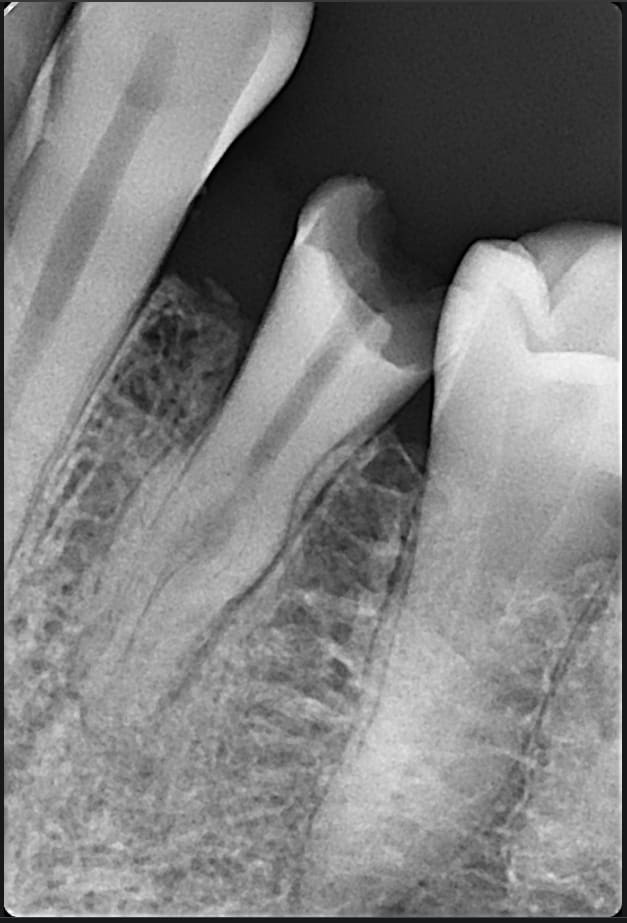

J'ai besoin de votre avis face à cette situation.

Je dénombre au moins 3 apex sur la rétro.

L'endo se tente ? Si oui comment ?

Très atypique, en effet!!

Ca me parait ingérable, sauf à être très délabrant pour l'accès, et donc se retrouver avec une racine inexploitable!

Par le passé j'ai déja traité avec succès des canines biradiculées. Avec une furcation plus haute et moins abrupte.

Dommage, ça se tente, en général un canal lingual qui descend tout seul, et deux vestibulaires un peu plus cotons à passer, mais là sur ta radio, ils sont bien visualisables, et l'angulation entrée canalaire/chambre n'est pas à 90°. Un beau challenge.